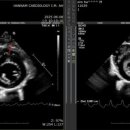

• 한남심장내과동물병원 | 한남심장내과동물병원 강아지 심장초음파 검진 내돈내산 후기

검사, 초음파검사, 혈액검사 proBNP, 혈액검사 Cardiac TnI 등등의 검사를 받고 약 2주 치를 받아서​ 총비용은 781,500원이 나왔습니다 ​ ....😭 ​ 한남심장내과동물병원 검진 후기 검사하고 결과를 듣고 약을 받는 데까지 약 두 시간 정도 소요되었어요​ 그리고 당일에 검진 결과서와 초음파 자료를 정리해서 메일로 전달...

산소포화도가 많이 낮지 않아서 산소를 쐬지 않고 검사를 진행했어요 ​ ​ 심장초음파를 보면서 설명해 주시는 원장님 ​ ​ 저번에 방문해서 처방 받았던 약을 먹고...물도 떠 주셨어요👍🏻 패드는 실수를 할까봐 저희가 깔았답니다! ​ 진심동물내과심장병원 대구광역시 수성구 동대구로 346 서한포레스트 상가동 1층(대로변에서...